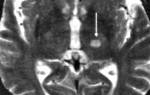

В первую очередь, врач должен узнать о месте работы больного, ведь ИС – это обычно профессиональное заболевание. Также специалист обязан назначить рентгеноскопическое исследование сустава плеча для выявления остеофитов или поражения акромиальной полости. Если у больного произошел разрыв сустава, нужно провести трехмерный рентген. Чтобы обнаружить разрыв манжеты, специалисты назначают артрограмму. Во время процедуры больному в сустав вводят специальный состав. Если он вытекает из субакромиального пространства, то результат исследования считают положительным – манжета порвана.